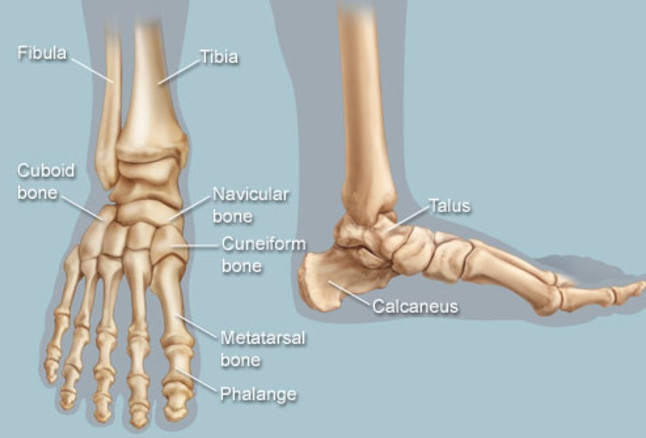

پاها به 3 بخش تقسیم می شوند :

- بخش جلویی پا ، حاوی 5 انگشت و 5 استخوان است .

- بخش میانی ، مجموعه ای هرمی شکل از استخوانهایی می باشد که قوس پا را تشکیل می دهند که شامل 3 استخوان میخی ، استخوان مکعبی و استخوان زورقی یا ناوی می باشد .

- بخش عقبی پا ، پاشنه و قوزک پا را تشکیل می دهد . استخوان مچ پا از استخوانهای ساق پا ( درشت نی و نازک نی ) پشتیبانی می کند و قوزک را تشکیل می دهد . استخوان پاشنه ، بزرگترین استخوان در پا می باشد .